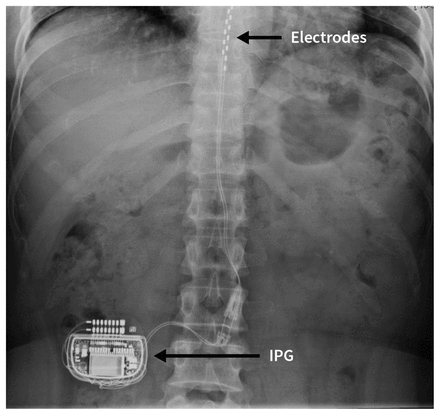

Initially, spinal cord stimulators were implanted by spine surgeons, necessitating general anesthesia, laminectomy, electrode placement directly onto dura, and postoperative hospital admission. Over the last decade, development of percutaneous epidural leads inserted under fluoroscopic guidance has enabled specially trained anesthesiologists or other pain specialists to safely implant spinal cord stimulators as outpatient procedures, using light sedation and local anesthesia (Figure 2).

Spinal cord stimulation consists of leads placed in the epidural space alongside the dorsal column and then tunnelled subcutaneously to an implantable pulse generator. These generators contain a battery and microprocessor (similar to a pacemaker) that are internalized within a subcutaneous pocket either within the abdominal wall or posteriorly in the flank or gluteal region, and programmed transcutaneously while allowing remote control by the physician or patient. Implantable pulse generators last 5–10 years, depending on rechargeability, and are replaceable. Patients are asked not to twist, bend or stretch excessively for 6–8 weeks postoperatively. After this period, patients may resume most physical activities.